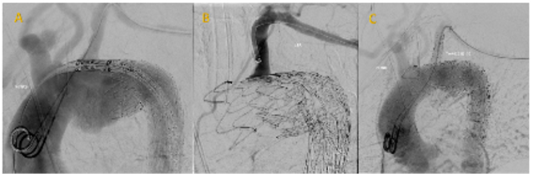

A surgical arterial cutdown was performed at the brachial artery, and an 8-French steerable sheath was placed (Lifetech® FuStar™) at the level of the left subclavian artery (LSA) origin. A LifeTech® FluThrough™ 20-gauge needle system was used to achieve a fenestration at origin of the LSA. The fenestration was enlarged with 6mm and 8mm non-compliant balloons and was finalized with the deployment of a balloon-expandable covered stent (Gore® Viabahn Ballon-Expandable™), Figure 3. Completion angiography showed patency of the LSA and no apparent endoleaks.

Figure 3 Intra-operative angiograms.

(A) Shows the loss of priximal seal of of previosuly implanted graft. (B) After achieving proximal seal, a sheath was inserted through the LSA perpincidular to the greater curvature of the aortic arch. (C) After punctering the endograft and dilation of the fenestration, a balloon-expandable covered stent is placed with exclusion of the arch lesion.